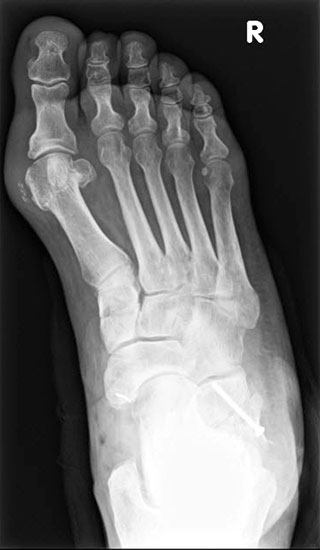

Radiologisches Beispiel einer fixierten Planovalgus Deformität Stadium III, 51 jähriger Patient. Stehendes präoperatives Röntgenbild und 1 Jahr postoperatives Röntgenbild des Fußes seitlich. Die Korrektur der Deformität umfaßte eine leicht korrigierende U

Abbildung 12